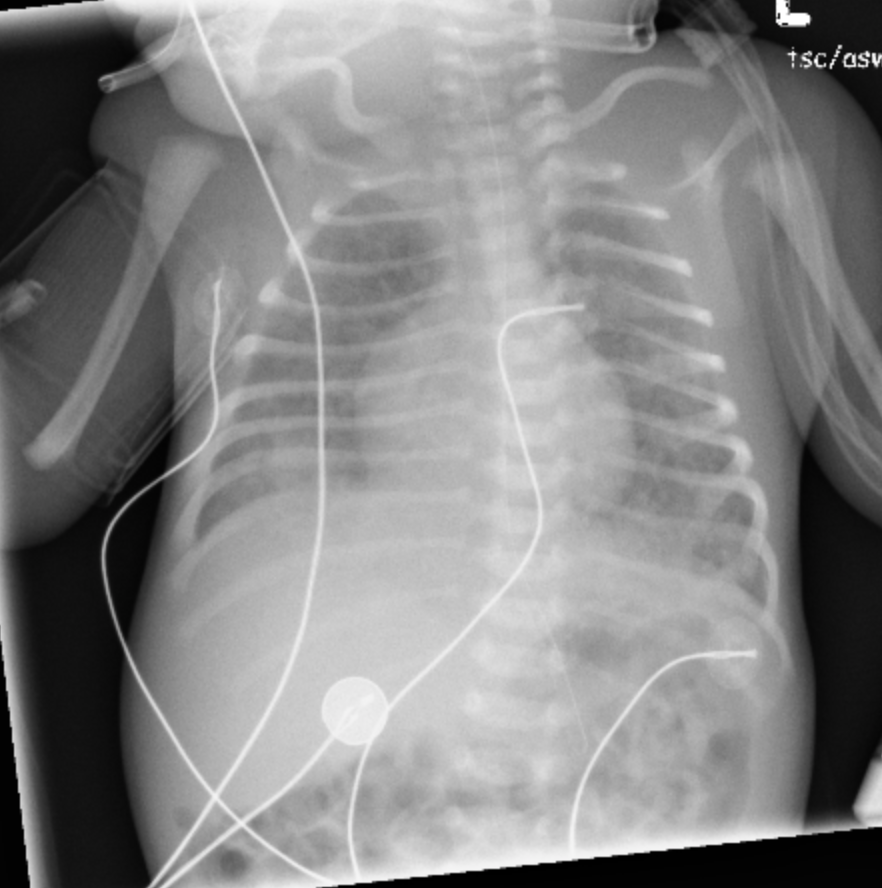

Bronchopulmonary Dysplasia

• Seen in premature babies, >3-4 weeks after birth (>4 weeks old give/take)

• Lungs damaged by prolonged mechanical ventilation

• Trach is a good clue

• Coarse markings with intermixed bubbly lucencies

• Markings gradually decrease over years

• Wilson-Mikity = BPD but no hx of mechanical ventilation